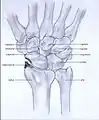

Post-traumatic osteoarthritis can be classified into four stages.[1][6] These stages are similar between SLAC and SNAC wrists. Each stage has a different treatment.

- Stage II: the osteoarthritis is localized in the entire radioscaphoid joint.

Stage II